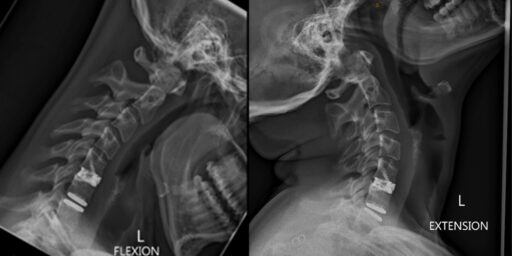

Study Overview Cervical total disc replacement (CTDR) involves removal of the damaged cervical disc and replacement with an artificial device that is designed to maintain normal neck movement and relieve symptoms. While CTDR can help many patients, some patients experience problems over time such as recurring pain or discomfort in their neck and/or arms. Other […]